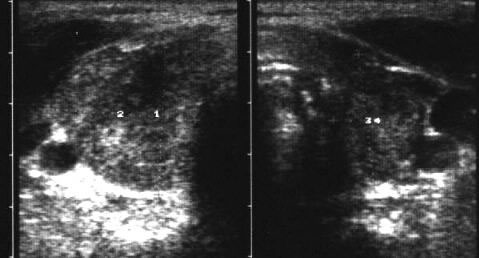

L’esame ecografico è diagnostico di tiroidite evidenziando vari gradi di ipoecogenicità diffusa o focale, a contorni sfumati, (gradi G1-G4 di Sostre) che possono interessare l’asse lobare anteriormente o posteriormente, la base lobare con successivo coinvolgimento dell’intero asse lobare etc.

Durante l’esame ecografico il paziente accusa vivo dolore durante l’esplorazione del lobo flogosato.

L’ipoecogenicità può coinvolgere, come già detto, tutta la ghiandola o aree focali, a contorni sfrangiati e irregolari, talvolta con aspetto di pseudo-nodulazione.

Tali aree pseudo nodulari hanno contorni sfumati con vascolarizzazione scarsa all’ecocolordoppler.

L’ecografia permette di monitorare tali aree flogistiche evidenziando la modificazione dimensionale delle aree ipoecogene e il coinvolgimento asincrono di zone diverse dello stesso lobo o dei due lobi in successione.